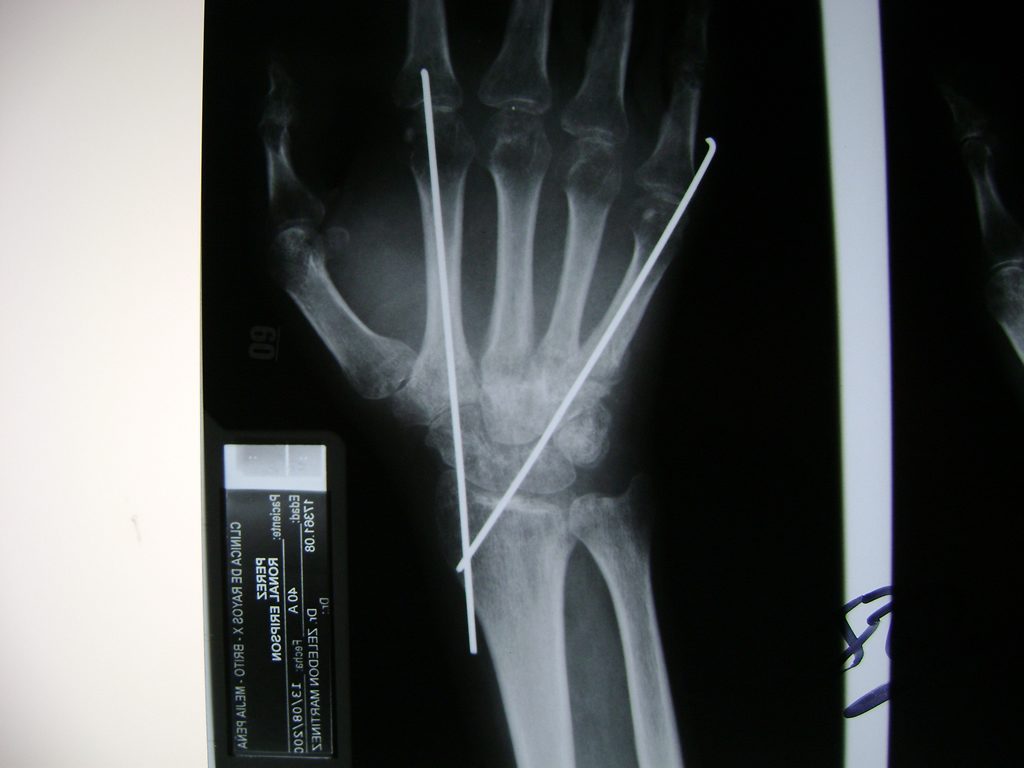

Cirugías de Húmero - Cirugías de Muñecas y Manos

Los procedimientos más comunes en cirugía de la mano son aquellos destinados a reparar traumatismos, incluyendo lesiones de tendones, nervios, vasos sanguíneos, y articulaciones; huesos fracturados; y quemaduras, cortes, y otros daños de la piel.